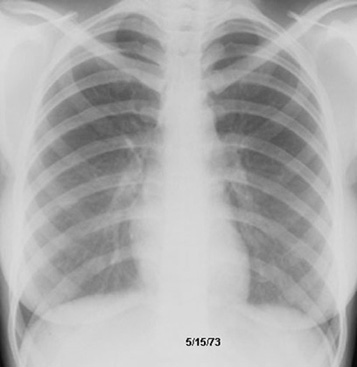

Sarcoidosis Spontaneous regression

Pulmonary function improved along with radiological clearance.